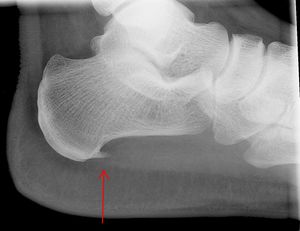

아침에 일어나서 처음 몇 걸음이 매우 아프지만, 곧 괜찮아지고, 오랫동안 앉아 있다가 갑자기 걷기 시작하면 아프며, 뒤꿈치 뼈의 앞쪽 안쪽을 누르면 매우 아픈 부위가 있는 등의 증상이 족저근막염의 특징이다.[40] X선 촬영에서 뼈의 돌출부(골극)가 확인되는 경우도 있지만, 통증의 원인이라고 단정할 수는 없다.[45]

뒤꿈치 박차는 족저 근막염 환자의 최대 50%에서 발견되는 종골(뒤꿈치 뼈)의 작은 뼈 석회화이다.[4] 하지만 뒤꿈치 통증의 원인은 뒤꿈치 박차 자체가 아니라 족저 근막염이다.[13]

의료 영상 검사는 대개 필요하지 않으며, 비용이 많이 들고 족저 근막염 치료에 큰 영향을 주지 않는다.[16] 진단이 불확실한 경우, 피로 골절이나 골극 발생 등 다른 원인을 확인하기 위해 발목 측면 X-레이 촬영을 할 수 있다.[5]

아침에 첫 걸음을 뗄 때, 오랫동안 앉아 있다가 갑자기 걸을 때 심한 통증이 있고, 뒤꿈치 뼈 앞쪽 안쪽을 누르면 아픈 부위가 있는 등의 증상은 족저 근막염의 특징이며,[40] 비교적 쉽게 진단할 수 있다.[42] X선 촬영에서 뼈 돌출부(골극)가 확인되기도 하지만, 이것이 통증의 원인이라고 단정할 수는 없다.[45] 40세 이전, 뒤꿈치 뼈 앞쪽이 아픈 경우, 아침보다 저녁에 통증이 심하거나, 걸을수록 통증이 심해지면 다른 질병일 수 있다.[40]